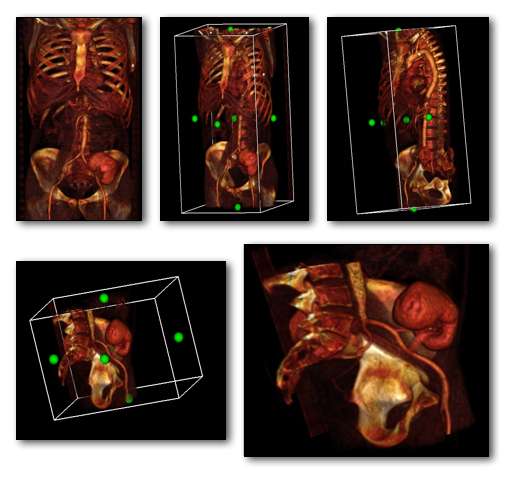

A final feature to note about volume rendering is that 3D editing techniques can be applied so as to exclude unwanted features from the computations and to expose internal structure. This is illustrated in the following figure, where planes of an orthogonal frame can be moved to crop the voxel data from six directions.